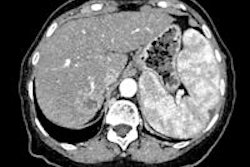

Even though incidental focal liver lesions are mainly benign, they may present with equivocal enhancement patterns on contrast-enhanced CT or MR. This may occur because of incorrect scanning time or the true presence of atypical contrast enhancement or persistent lesion hypovascularity during the different dynamic phases, Quaia said.

For inclusion in the study, each lesion had to present as equivocal or atypical enhancement during the arterial phase at contrast-enhanced CT/MR, or demonstrate hypovascularity on the portal late-phase or with persistent hypovascularity during all dynamic phases, Quaia said. In addition, contrast-enhanced ultrasound had to be performed within 25 days of the CT and/or MR exams.